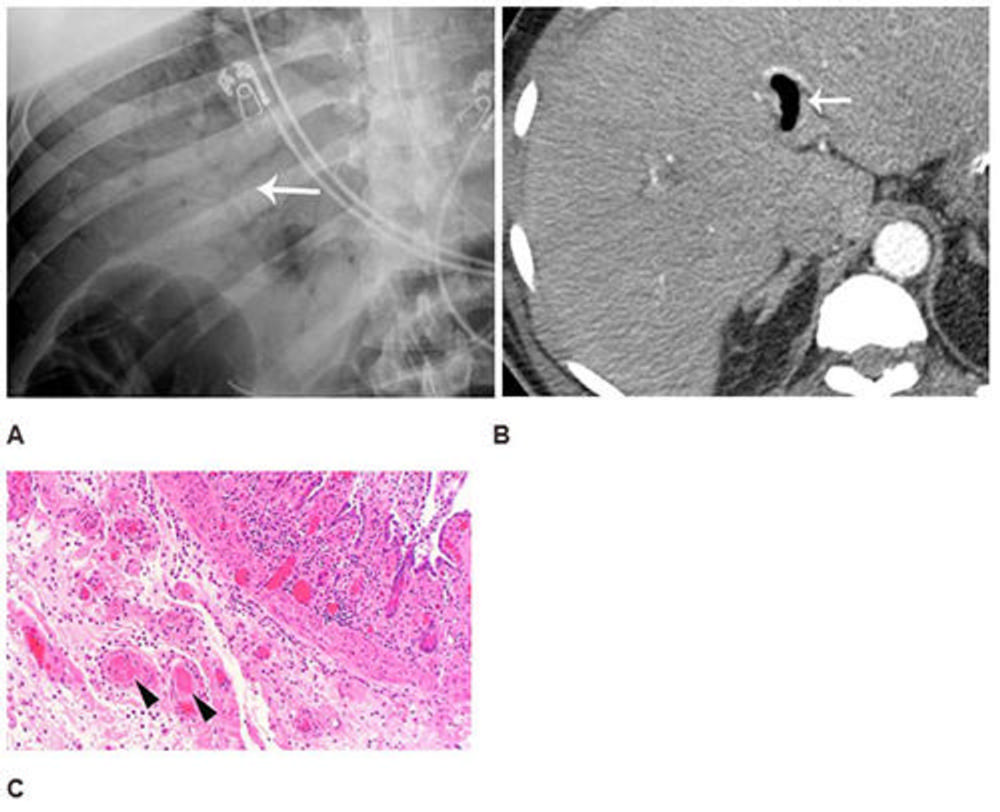

Figure 3. Abdominal radiograph (A) in a 52-year-old man demonstrates portal venous gas (thin arrow in A), suggestive of bowel infarction. Post-operative CT (B) also demonstrates portal venous gas (thin arrow in B). At laparotomy, ischemic and necrotic bowel was identified along with an atypical yellow discoloration of small bowel. Photomicrograph (H and E, 400x) (C) demonstrated submucosal arterioles with fibrin thrombi (arrowheads). The overlying mucosa (upper right) is partially necrotic with crypt dropout and partial loss of the surface epithelium.